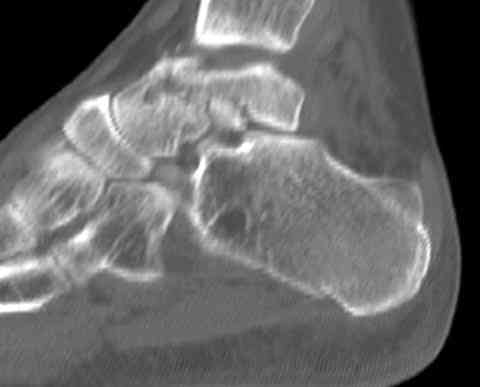

Случай с множественным оскольчатым переломом тарана оперированный из двойного доступа.

Через 14 мес.: